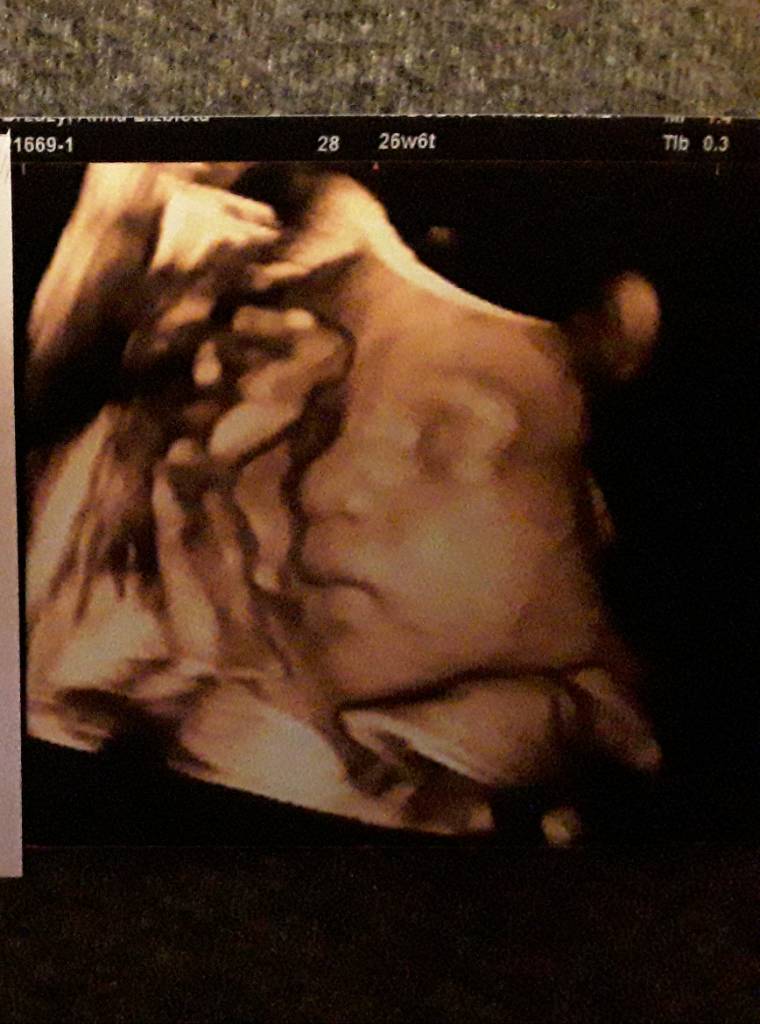

Hej, ja też po wizycie. Wszystko w porządku, na dole trzyma wszystko. Malutka ma już swoj pierwszy 1000g. Pomiary odpowiadają obecnemu tygodniowi. Miałam też Ktg i wszystko w porządku [emoji846] dostałam też piękne zdjęcie 3d i nie mogę przestać na nie patrzeć [emoji173]

20190205_214837.jpeg

W szoku jestem bo niby tylko kilogram, a już taka buzia ukształtowana. Jakby miała się zaraz urodzić. Nie mogę się napatrzec [emoji7]